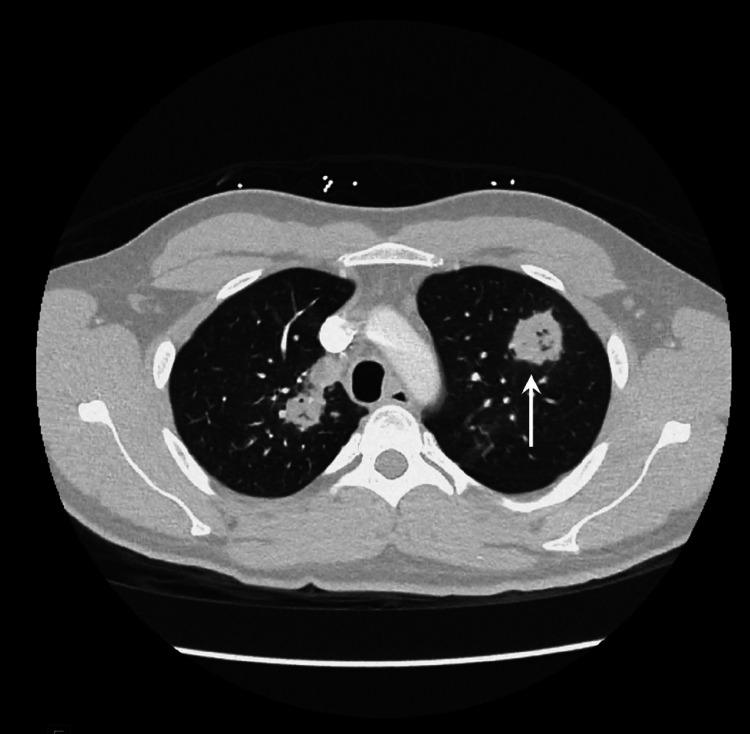

Granulomatosis with polyangiitis (GPA), formerly named Wegner's granulomatosis is an antineutrophilic cytoplasmic antibody (ANCA) associated vasculitis of the small vessels. GPA can affect several organ systems even though predominantly affects respiratory and renal systems. Pathogenesis is initiated by activation of the immune system to produce ANCA, Cytoplasmic (C-ANCA) antibody, which thereby leads to widespread necrosis and granulomatous inflammation. Multisystem involvement with varied symptomatology makes GPA diagnosis more challenging. Early diagnosis and management are vital and can alter the prognosis of the disease. We present a literature review and a clinical scenario of a 26-year-old male with a history of chronic sinusitis, testicular carcinoma in remission, recent onset of worsening cough, epistaxis, hoarseness of voice, weight loss, and dark-colored urine. Workup revealed high titers of C-ANCA, C-reactive protein, procalcitonin, CT chest evidence of mass-like consolidation, and bronchoscopy findings of friable tissue that was not amenable for biopsy. Methylprednisolone and rituximab (RTX) were administered, which resulted in marked clinical improvement. Therefore, a keen eye for details is necessary to diagnose GPA early, which can improve disease outcomes dramatically.

摘要